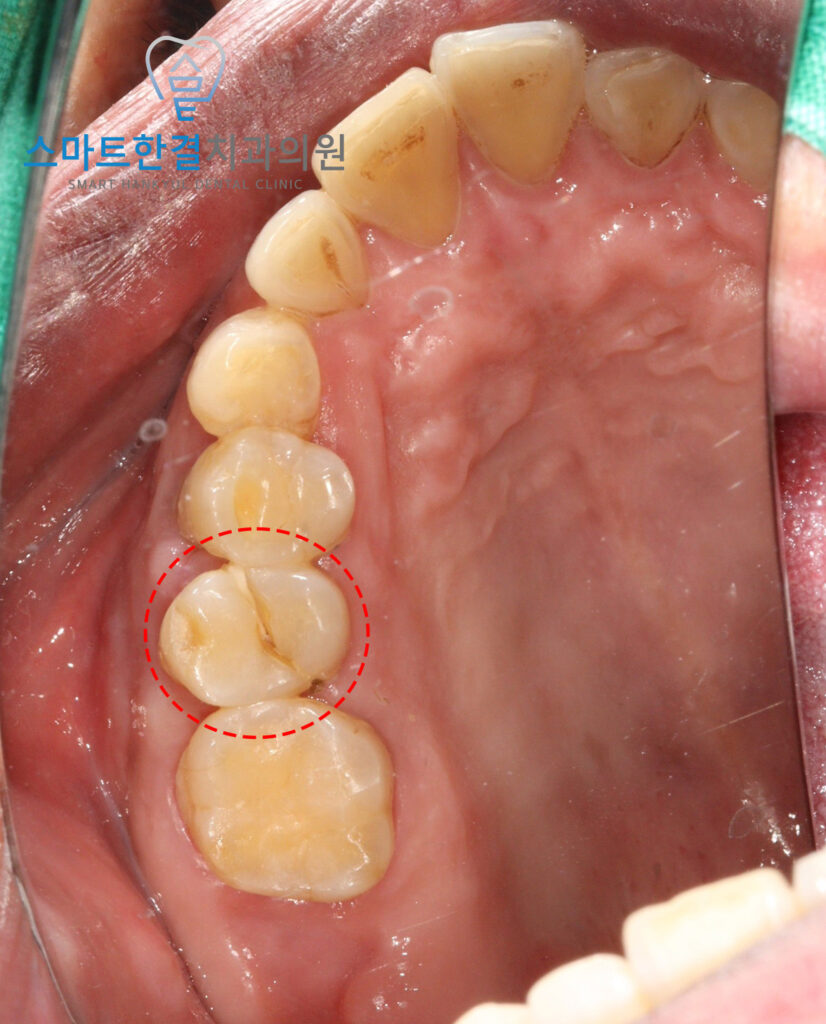

위 환자분께서는

처음 내원하셨을 때,

오른쪽 위 송곳니가 아프다며

내원해 주셨어요.

확인을 해보니,

송곳니가 아닌 두번째 작은 어금니의

파절이 관찰되었는데요.

육안으로 보기에도

파절선이 명확하여

치아 뿌리까지 금이 진행된

수직파절이 강하게

의심되는 상황이었어요.